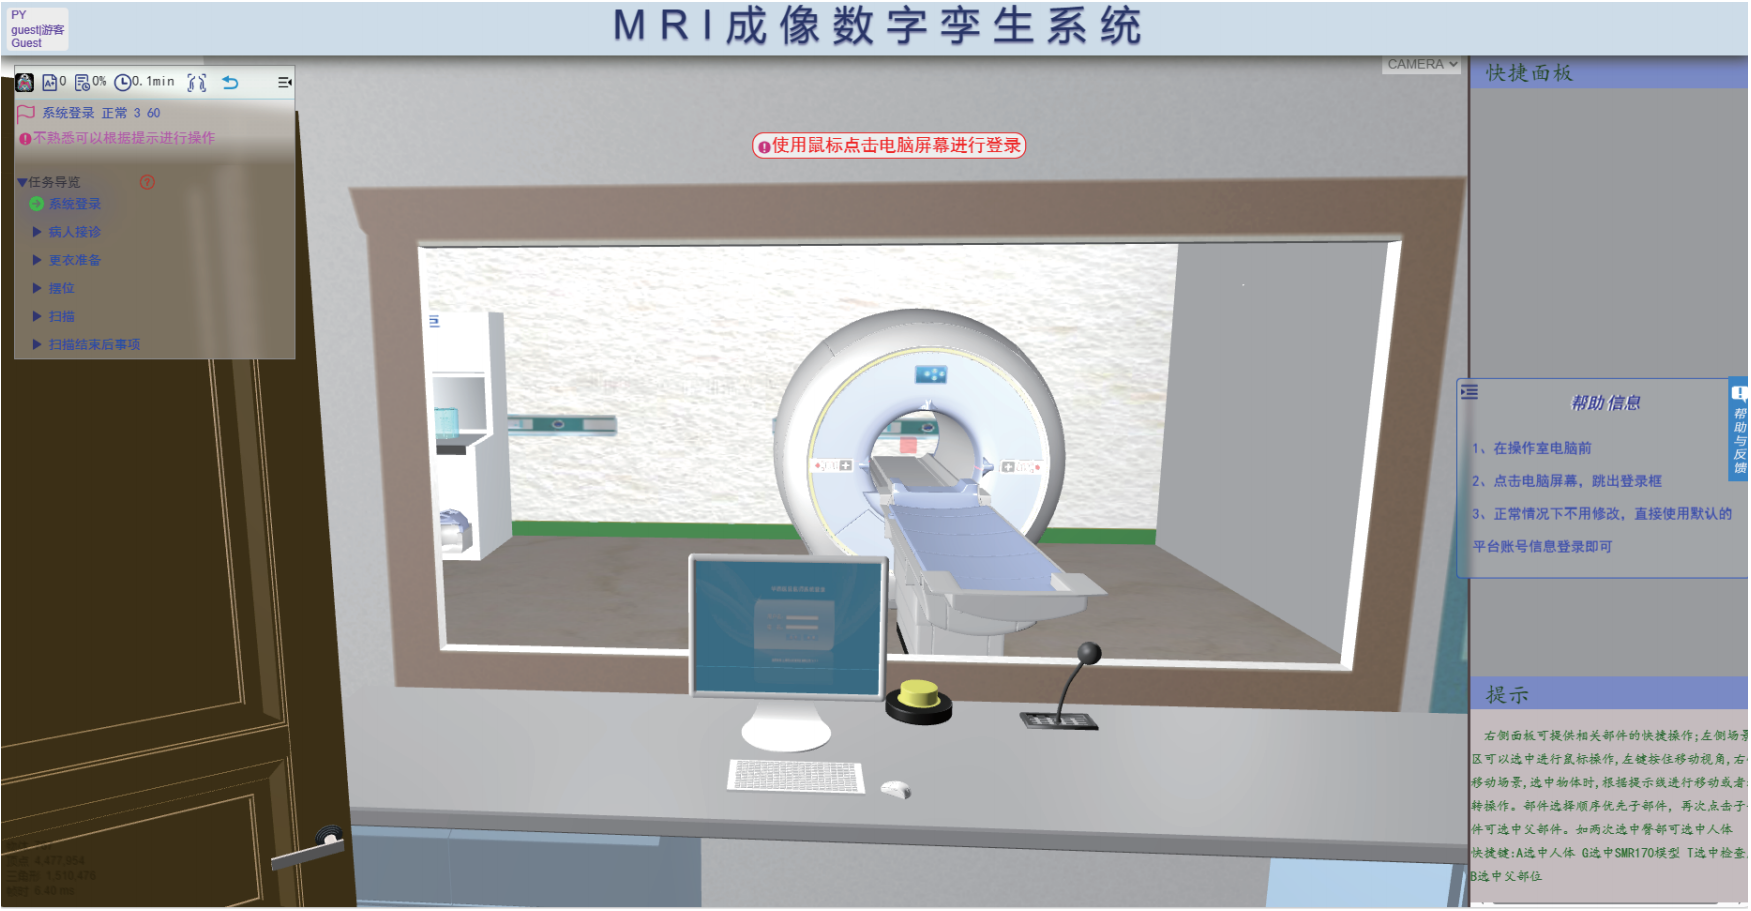

MRI成像数字孪生系统

基于数字孪生技术,研发了MRI成像数字孪生系统,模拟常见影像设备,设备操作与真实设备相同,达到使用者如同使用真实设备的效果。本场景基于真实的核磁检查流程所设计,扫描过程根据物理数字人实时计算MRI图像,包含参数可调、伪影模拟、故障诊断等各种强大功能。

基于数字孪生技术构建的 MRI 检查技术模拟系统,实现了机理与场景的深度融合,操作逻辑与真实设备完全一致,打造高度逼真的虚拟检查环境。虚拟场景完整复现 MRI 检查全流程,从技师登录、叫号、查验检查单、引导患者更衣等事项,到线圈选择、摆位、序列与参数设置等环节均细致还原。

系统内置基于人体摆位和参数的标准数据库(数据源自临床规范与专家共识),可对操作全过程进行精准量化评分,确保实训考核的标准化。此外,系统支持模拟灯芯绒伪影、化学位移伪影、运动伪影等十余种常见伪影,并可针对不同伪影设置考核场景,要求操作者制定并执行相应处理方案,强化对影像质量控制能力的培养,助力医学影像技术专业学生提升临床实操与问题解决能力。